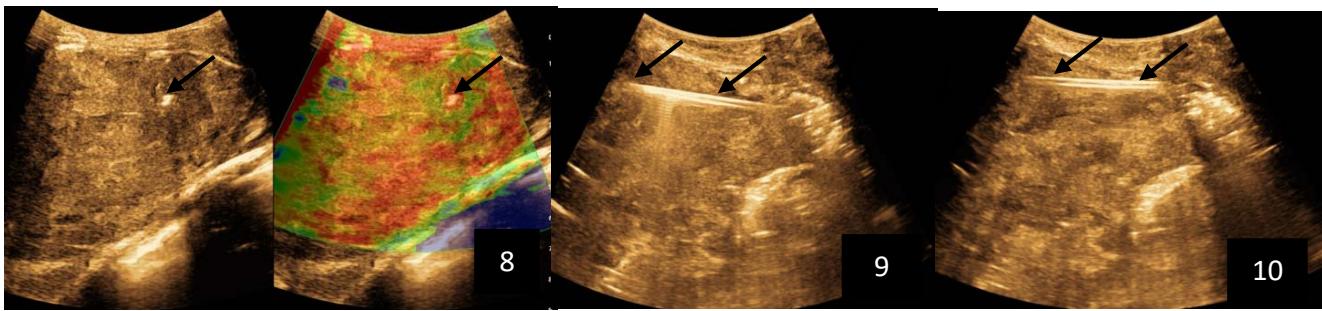

Iconography 1: 54-year-old patient with an intra-splenicsolid mass, anatomopathologically compatible with lymphoma: images 1 and 2: right pleurisy of moderateabundance, image3: celiacadenopathy, image 4: free ascites of moderateabundance, images 5 and 6: intra-splenicsolid mass of around $1418.16\mathrm{ml}$ in B mode and elastographyshowing areas of tumourrigidity, images 7-10: oblique linear images, showingbiopsy gun tracks.

Iconography B: 1 to 4: ultrasound images in mode B showing a large size, 5: ultrasound image in mode B showingsolidhyperechogenic nodules under the capsulorhexis, 6 to 10: ultrasound images in mode B showinglinearhyperechogenic images without overlay in relation to the trajectories of the aiguilles of biopsy.